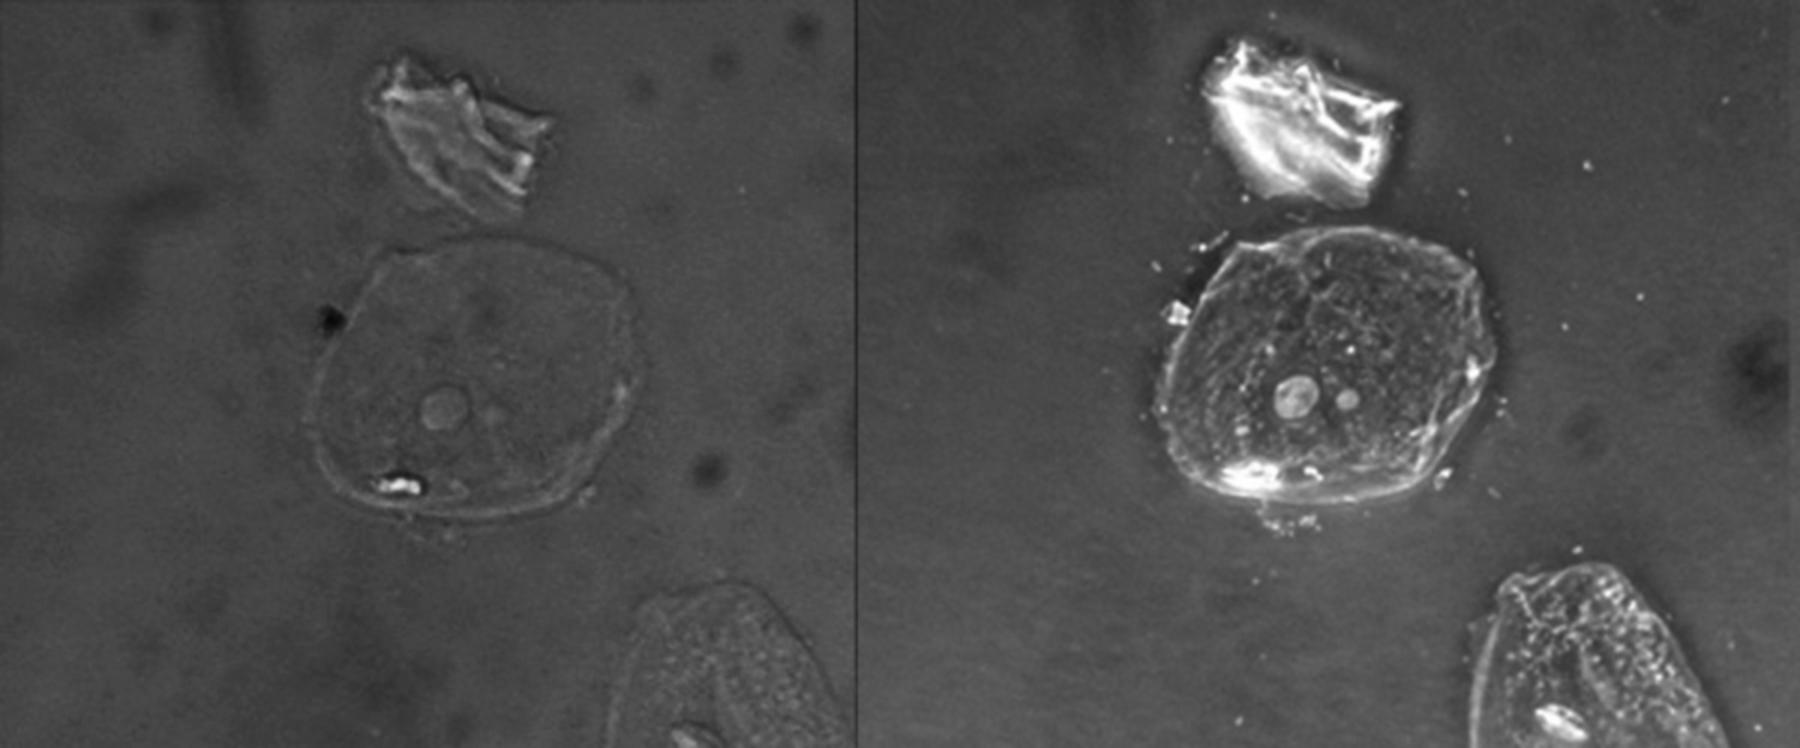

Brightfield Image (Left): This represents the standard form of optical microscopy where light is transmitted directly through the specimen. Because the biological tissue is unstained and translucent, there is very little contrast between the cell and the surrounding medium, rendering the structures nearly invisible and difficult to analyze.

Phase-Contrast Image (Right): This image utilizes an optical technique that converts phase shifts in light passing through a transparent specimen into brightness changes in the image. This process enhances the contrast of the cell borders and internal organelles, causing the cell to appear to “glow” against the dark background and revealing details like the nucleus.

Simple Squamous Epithelial Cells: These are the primary subjects located in the center and bottom right of the viewing field. They are characterized by their flattened, scale-like appearance and a central nucleus, serving as a thin barrier in various anatomical locations to facilitate diffusion and filtration.

Acellular Debris: This irregular artifact is located above the central cell in both images. It represents non-living particulate matter, which is common in slide preparations and can be distinguished from viable cellular material more easily using high-contrast imaging techniques.

In the phase-contrast image (right), the nucleus is clearly visible as a denser, circular structure within the cytoplasm. The nucleus houses the cell’s genetic material (DNA) and coordinates cellular activities such as growth and metabolism. The cell membrane is also sharply defined, marking the boundary between the intracellular environment and the extracellular space. In a clinical context, observing the nucleus-to-cytoplasm ratio and the regularity of the cell border is essential for detecting abnormalities, such as precancerous changes.

In contrast, the phase-contrast image reveals the refractive index variations within the cell. The nucleus is denser than the surrounding cytoplasm, and the cytoplasm is denser than the mounting medium. As light passes through these different densities, it is shifted out of phase. The phase-contrast microscope amplifies this shift. The result is an image where the cell membrane and nucleus appear darker or brighter (depending on the specific setup) than the background. This “halo” effect, often seen around the edges of the cell in phase-contrast images, is an optical artifact but serves as a helpful outline for identifying the cell’s perimeter.